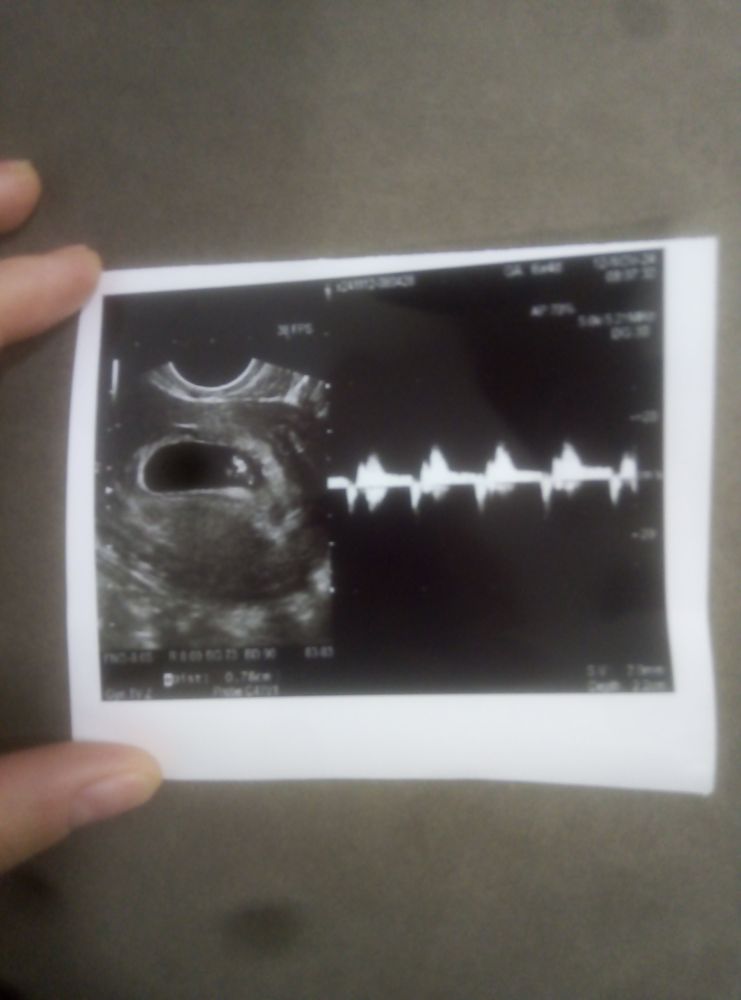

Первое УЗИ

Слава Богу креветочка растёт хорошо))) Сердечко бьётся (очень переживала, что не услышу его) Правда у меня нашли гематому (ну возраст у меня, что поделаешь))) Будем лечиться=)) Но в общем я очень рада, сердцебиение 146) :)